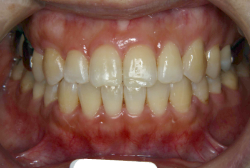

「左奥歯でものが噛めない」という主訴で来院したケースです。診断の結果、基本的には「叢生」という隙間が足りないと言うことが原因の凸凹症例でしたが、左下の乳歯が高校生になってもまだ残存している状態で、そのせいで噛み合わせが極端に悪くなっていました。

検査の結果、乳歯の下には後継ぎの永久歯が先天的に欠如していました。配列の凸凹が厳しく非抜歯で矯正することは難しく、仮に無理をして非抜歯治療をしても後々「後戻り」が懸念されることから、このような症例の場合は通常、上下顎左右第一小臼歯を抜歯させていただくのですが、左下は乳歯を抜歯して、第一小臼歯は残すことにしました。これで結果として、小臼歯部を上下左右で一つずつ減らしたのと同じ状況になります。治療後は歯並びが綺麗になっただけでなく、噛み合わせ的にも正しい状態が確立しています。

このように、先天的に永久歯が足りないという症例は最近増えています。親知らずはなくても特に問題になりませんが、その他の歯が足りないと言うのは審美的にも機能的にも重大な障害となります。しかし、矯正治療を正しく行えば、結果として歯がすべてあった場合と全く同じ仕上げにすることも可能です。